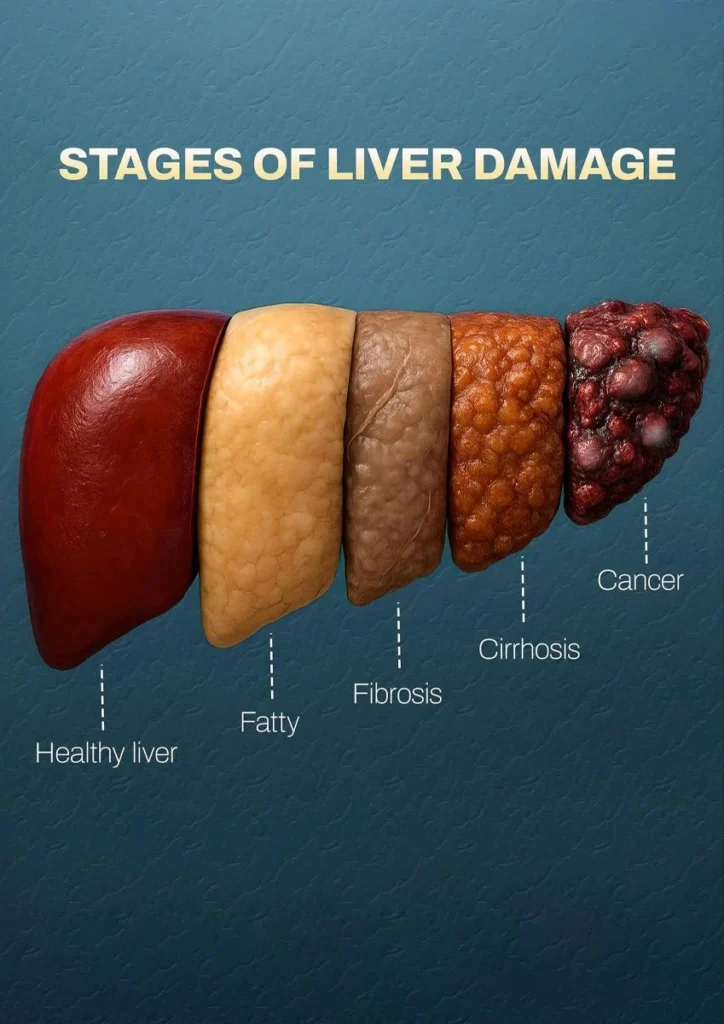

➡️ Getting worse, leading to severe scarring (cirrhosis) or liver failure

When your liver is stressed for too long, it starts to get scars and turn hard like a rock (what doctors call Fibrosis)

This herb acts like a softener… stopping those scars from forming and preventing your liver from turning into a useless piece of wood.